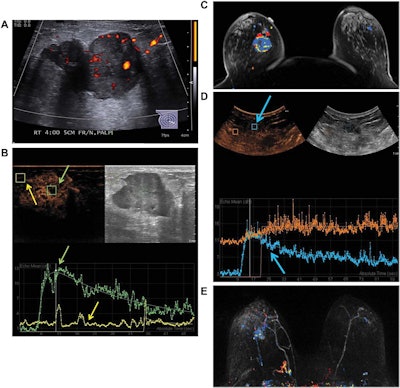

Images are from a 50-year-old woman presenting with a right breast lump that has biopsy-proven infiltrating ductal carcinoma. A: Targeted right-breast ultrasound imaging showed an oval hypoechoic mass with indistinct margins measuring up to 3.7 cm. B: At baseline before starting neoadjuvant chemotherapy, CEUS showed an avidly enhancing tumor (green arrows) with tumor peak intensity on the time-intensity curve generated by the Qlab software. The region of interest was placed on adjacent normal breast tissue (yellow arrows), which had a flat line on the time-intensity curve. The y-axis of the time-intensity graph corresponds to the intensity or mean echo (decibels), whereas the x-axis corresponds to the absolute time (seconds). C: Axial postcontrast fat-saturated MRI at baseline showed an enhancing tumor with mixed kinetics in the right breast. After neoadjuvant chemotherapy was completed but before surgery, contrast-enhanced and MRI scans were again performed. D: CEUS showed a 2-cm residual enhancing tumor with a time-intensity curve (blue arrows) that had rapid enhancement and washout. E: Maximum-intensity projection contrast-enhanced MRI performed after neoadjuvant chemotherapy was completed showed a decrease in the size of tumor to 2 cm with predominantly progressive kinetics. At the time of right lumpectomy, this patient had 1.5 cm of invasive tumor in the right breast, consistent with a noncomplete pathologic response. Both the contrast-enhanced ultrasound and MRI studies predicted that there would be noncomplete pathologic response at the time of surgery. Images courtesy of the Journal of Ultrasound in Medicine.